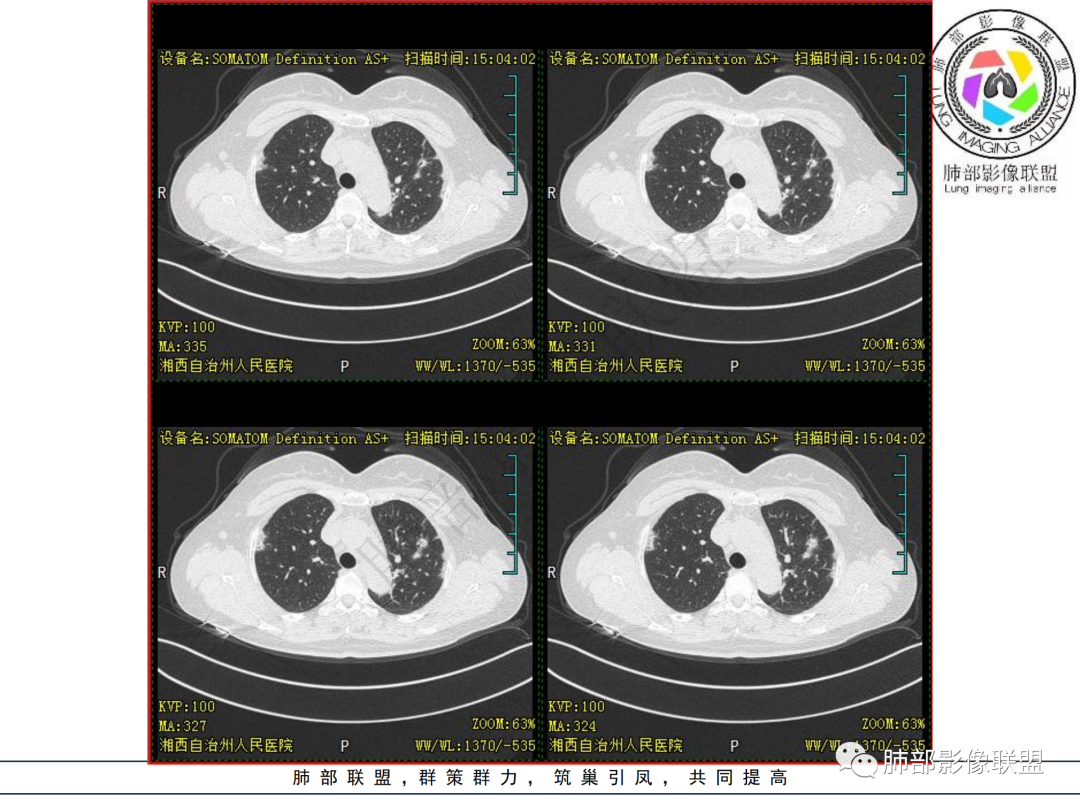

1.中年女性,发现双肺多发病变,且增多增大。

缺乏呼吸道症状及中毒症状,实验室炎性指标不高

既往多关节肿痛一年余,被诊断“类风湿”。此次就医无关节肿痛。

2.双肺多发片状影,胸膜下分布为主,部分沿支气管血管束分布,边界不清,实性及磨玻璃密度,趋于柔和,可见支气管进入或穿行,未见空洞、钙化及树芽等。部分病灶显示反晕。

3.未见腔积液。

4.双肺门及纵隔未见增大淋巴结。